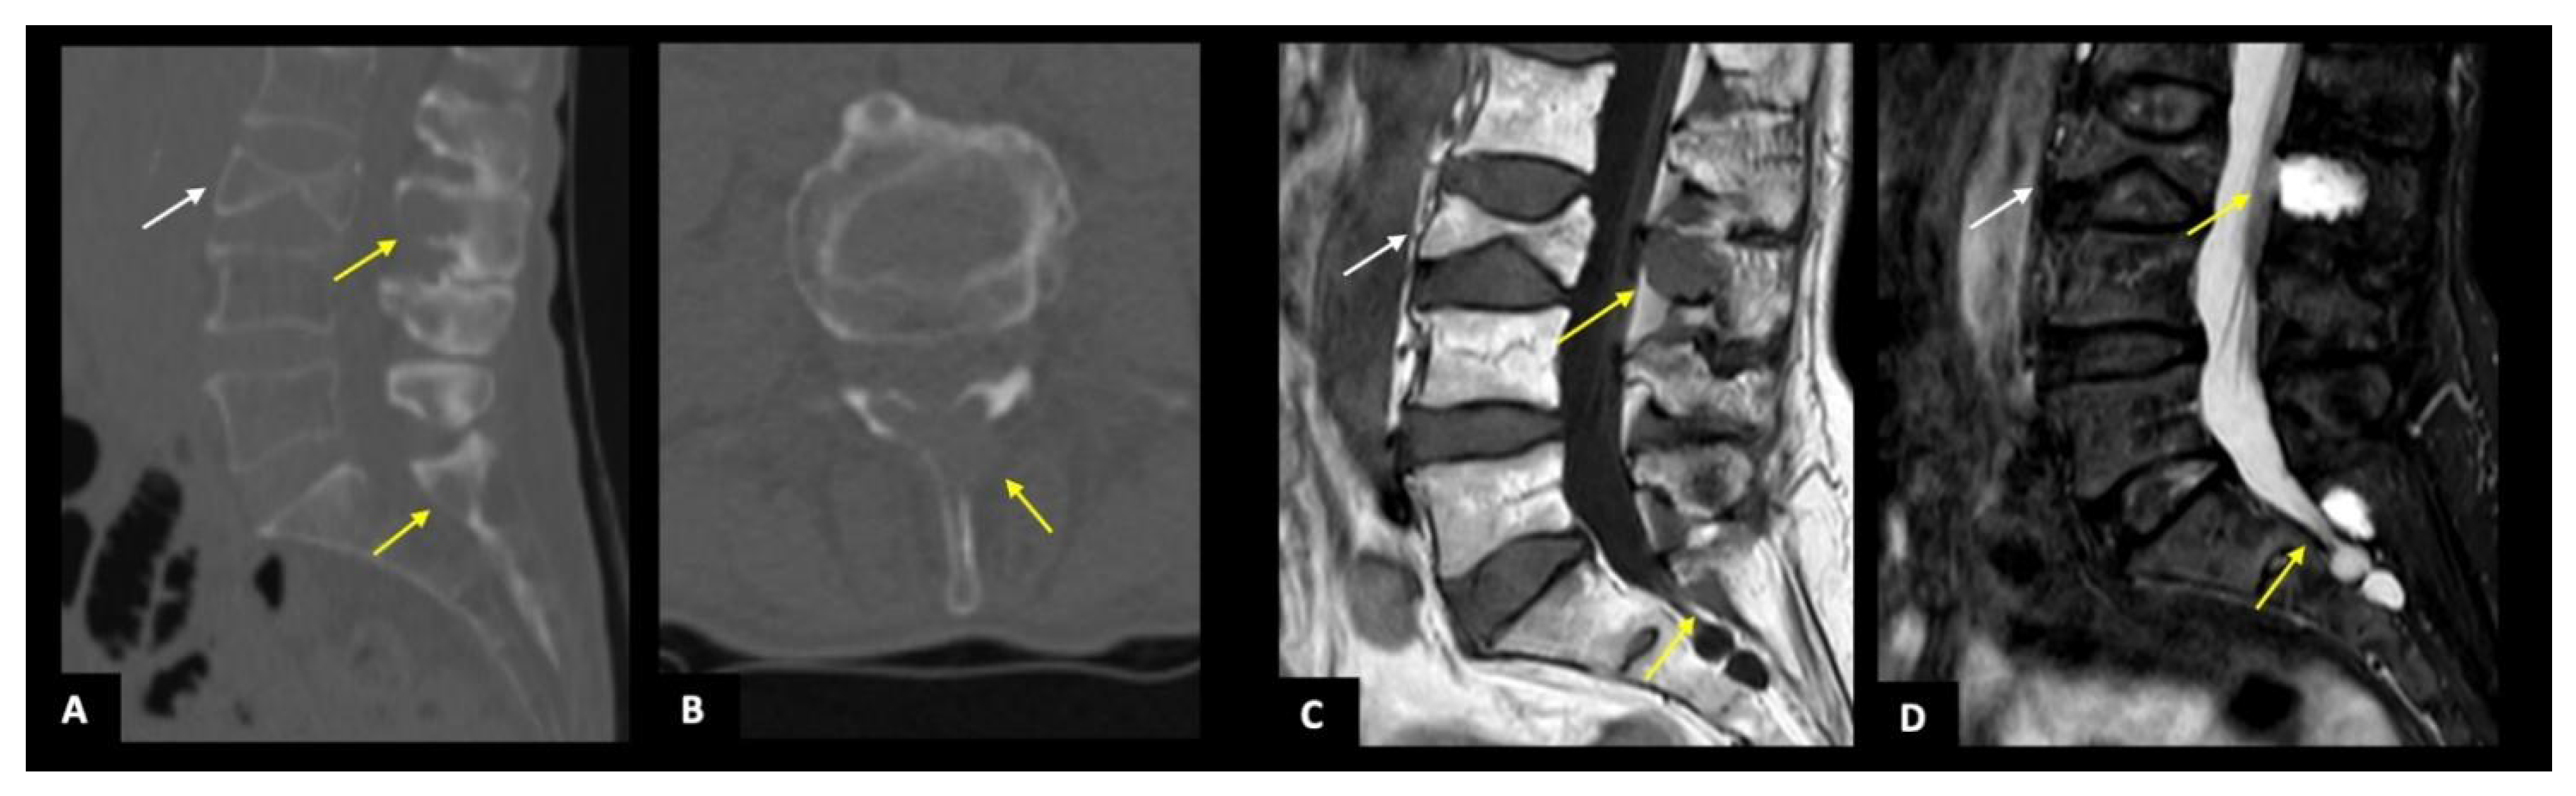

3.2. CT Findings

3.3. MRI Findings